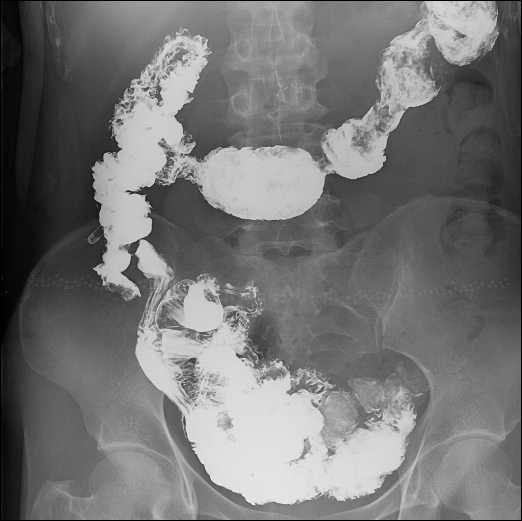

胃肠造影

肠道气钡双重造影

食道长轴、胃全景、胃小沟与胃小区局部放大精细数字图像、下消化道全景等;